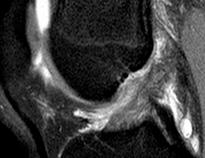

Dein Kniegelenk

In der Alltagssprache wird das Kniegelenk häu g nur als „Knie“ bezeichnet. Es ist das größte Gelenk des menschlichen Körpers mit einer ausgeklügelten Anatomie. Es wird den ganzen Tag teilweise mit dem Sechsfachen des Körpergewichts belastet. Laufen, Treppensteigen, Sitzen – in jeder Bewegung und sogar in Ruhephasen belasten wir das Kniegelenk mehr oder weniger stark.

Im Knie verbinden sich der Oberschenkel und der Unterschenkel miteinander. Genau genommen ist das Kniegelenk ein zusammengesetztes Gelenk aus zwei Einzelgelenken: dem Kniescheibengelenk zwischen dem Oberschenkelknochen und der Kniescheibe und dem Kniekehlgelenk zwischen dem Oberschenkelknochen und dem Schienbein. Das Zusammenspiel aus Knochen, Knorpeln, Muskeln, Sehnen und Bändern ergibt zusammen ein Dreh-Scharnier-Gelenk. Durch diesen Aufbau ermöglicht uns das Kniegelenk die Beugung und Streckung des Beins. Dabei gleitet die

Kniescheibe in einer speziellen schmalen Rinne über den Oberschenkelknochen. Die an ihr befestigten Sehnen des Oberschenkelmuskels werden durch diese „Zwischenlagerung“ auf Abstand zu den anderen umliegenden Knochen gehalten und scheuern so nicht direkt über das Gelenk. Außerdem wird damit eine Art Hebelmechanismus erzeugt, der die Kraftwirkung der Muskelaktivität verstärkt. Ob Inlineskater, Hockeyspieler oder früher Ritter in ihren Rüstungen – ein Kniegelenkschutz hat immer vorne ein rundes „Schutzschild“ für den obersten Teil des Kniegelenks, die Kniescheibe, die direkt unter der Haut liegt. Verschiedene Bänder oder auch Sehnen sorgen für die notwendige Stabilität und Beweglichkeit. Das vordere und hintere Kreuzband verläuft im Inneren des Kniegelenks zwischen den Enden des Oberschenkel- und Unterschenkelknochens. Sie sind permanent gespannt und stabilisieren das Kniegelenk bei Bewegungen des Beins, sodass es sich nicht nach vorne oder hinten verschiebt. Zwei Seitenbänder verlaufen an der Innen- und Außenseite des Knies und stabilisieren es

24 das Gesundheitsmagazin

/ INFORMATIV

bei seitlichen Bewegungen. Die Gelenkkapsel umhüllt alle Gelenkflächen und die Gelenkflüssigkeit im Innern stellt die Ernährung der Knorpelschicht sicher. Ohne Gelenkknorpel würde jede Bewegung des Knies sehr schmerzhaft sein, denn diese Schicht verhindert, dass die Knochen direkt aufeinander liegen und sich reiben. Überall, wo sich die Kniegelenksknochen berühren, sind diese Kontaktflächen mit einer mehreren Millimeter dicken, sehr glatten und elastischen Knorpelschicht überzogen, die als Puffer und Stoßdämpfer dient. Die halbmondförmigen Menisken zwischen Ober- und Unterschenkelknochen verteilen den Druck auf die Gelenkflächen optimal und gleichen die Unterschiede zwischen Oberschenkelknochen und Schienbein aus. Schwere Einkaufstaschen in die Dachgeschosswohnung tragen, in High-Heels stundenlang durch die Stadt flanieren, etliche Kilo zu viel auf den Rippen haben, lange Strecken bergab gehen, Fußball spielen - unsere Kniegelenke sind täglich hohen Belastungen ausgesetzt. Solange das Knie funktioniert wie geschmiert, macht sich darüber kaum jemand Gedanken. Doch das größte und komplizierteste Gelenk des Körpers ist besonders anfällig für Störungen, Verletzungen, entzündlichen Erkrankungen oder Knorpelschäden.

Je höher die mechanische Belastung, die auf ein Gelenk wirkt, desto anfälliger ist es für die Verschleißerkrankung Arthrose. Gonarthrose, der medizinische Fachbegriff für die Verschleißerkrankung des Kniegelenks, kann jeden treffen. Bei etwa der Hälfte aller Menschen setzt der Knorpelverschleiß bereits ab dem 35. Lebensjahr

ein. Spätestens ab dem 60. Lebensjahr bleibt kaum noch jemand davon verschont. Arthrose im Kniegelenk muss nicht zwangsläufig die Folge altersbedingten Verschleißes sein. Auch durch Verletzungen (z.B. Kreuzbandriss), Übergewicht, Überbelastungen oder Fehlstellungen (z.B. Xoder O-Beine) und die damit verbundene Fehl-belastungen kann ein Gelenk im Lauf der Zeit Schaden nehmen.

TEXT: Rüdiger Schmauder

FOTO: Shutterstock

“Bei etwa der Hälfte aller Menschen setzt der Knorpelverschleiß bereits ab dem 35. Lebensjahr ein”